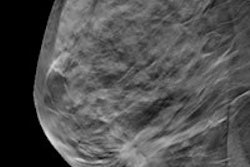

Researchers from the University of California, San Francisco (UCSF) analyzed 46,288 consecutive screening mammograms performed there. The team divided the exams into three groups: those interpreted without comparison with prior mammograms, those interpreted in comparison with one prior exam, and those interpreted in comparison with two or more prior exams (AJR, October 2016, Vol. 207:4, pp. 918-924).